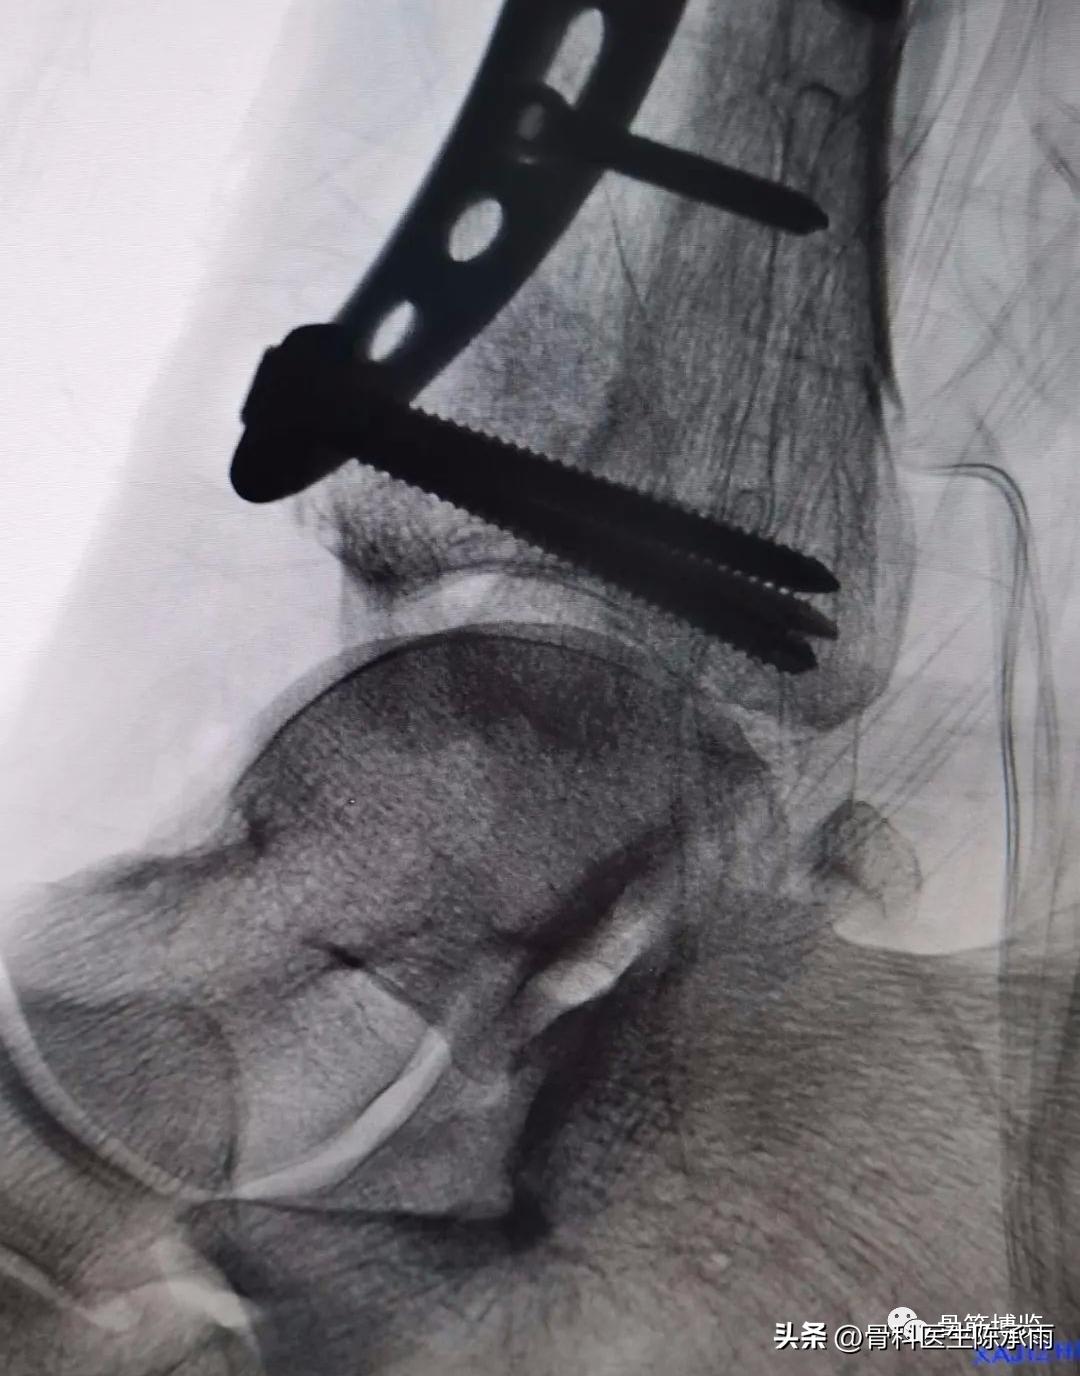

这是1例开放性胫腓骨多段骨折患者,胫骨远端pilo骨折(pilon骨折指累及胫距关节面的胫骨远端骨折,通常是指胫骨远端三分之一,波及胫距关节面的骨折,胫骨远端关节面严重粉碎,会出现骨质的缺失以及的远端松质植骨的压缩,并常合并有的腿骨下端的骨折以及严重的软组织挫伤。)

胫骨中段开放性骨折,一期行清创骨牵引,二期见骨创口愈合差,行远端骨折切开复位内固定,中段骨折行外固定架固定,必要时3月后视情况可改内固定。

术中C臂